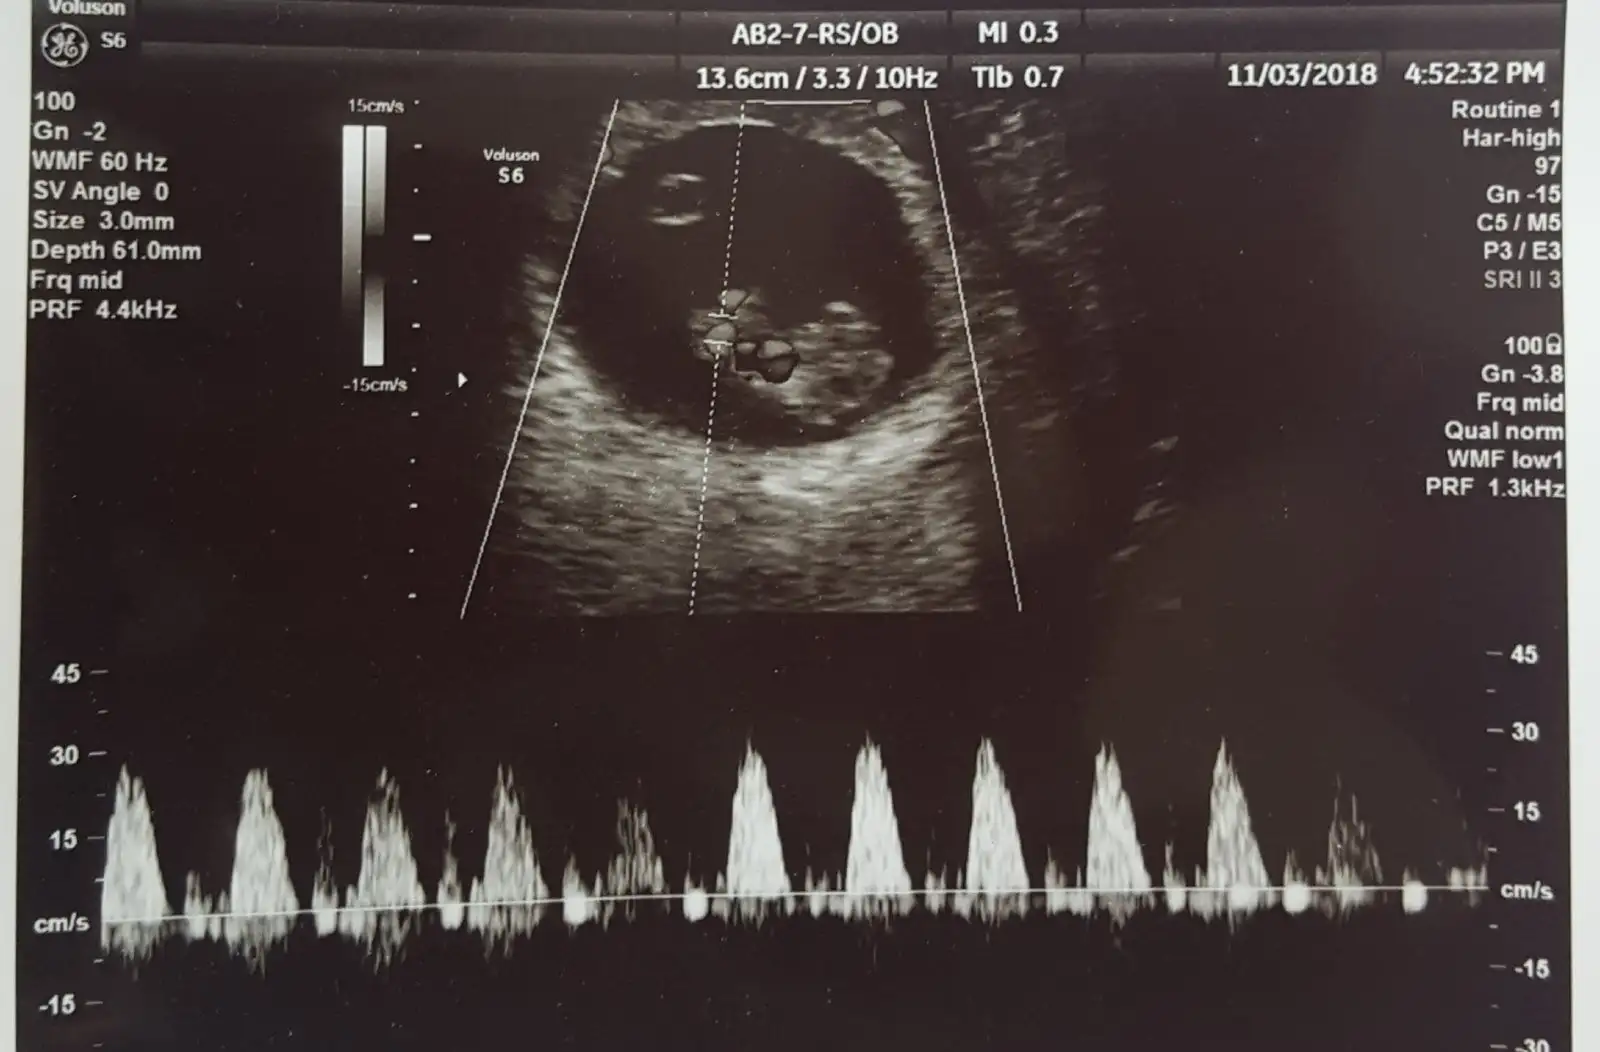

Kizlar cekirdegim buyumus gördüm geldim.sat ile tam uyumlu 9+3

20181103_170256.webp

Şimdi dün ben kontrole gitmiştim doktor 2 kese gördü demiştim hatta ama doktor sonra ama şuan çok küçük size tam birşey söylemiyorum saglikli bir gebelik var diye bile diyemem dış gebelik mı normal gebelik mı diye haftaya çarşamba tekrar gideceğim arastirmak istemiyorum ama kafama soktu doktor bir kere baktım kese varsa dış gebelik değildir diyenler var bide HCG düzenli artmiyorsa dış gebelik diyorlar benim öyle de değil valla kafam allak bullak:cry: